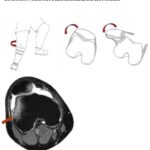

Luxación transitoria lateral de la patela

Dibujo que representa la rotación interna del fémur sobre la tibia con la rodilla flexionada, que originará la luxación transitoria lateral de la patela.

Imagen axial de secuencia potenciada en T2 con saturación grasa de la rodilla derecha en paciente con luxación transitoria lateral de la patela secundario a mecanismo de flexión y rotación interna del fémur. Contusiones típicas en la vertiente medial de la patela y en la superficie anterolateral del cóndilo femoral externo. Derrame articular en la bolsa suprarotuliana.

Fuente: https://epos.myesr.org/posterimage/esr/seram2014/124014/mediagallery/579038